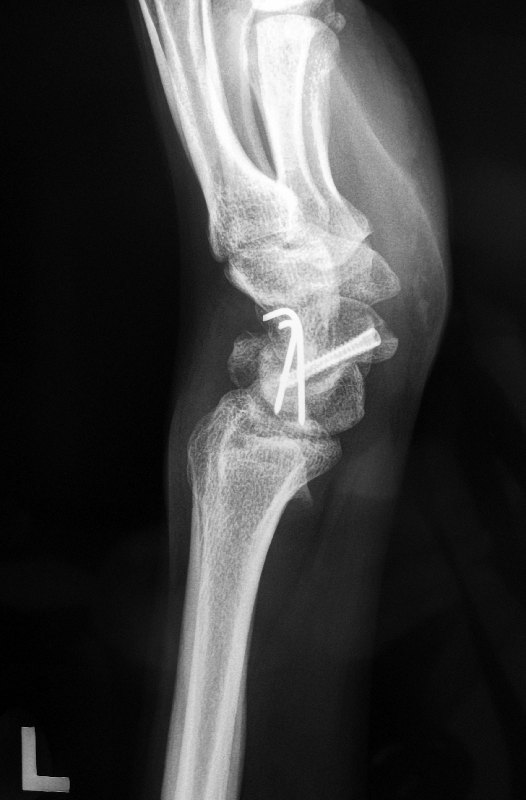

This is how the x-rays looked like after the surgery:

The fracture went on to heal over the next 2 to 3 months. This is how it looked like after the scaphoid fracture had healed.

The 2 wires along the luno-triquetral joint were surgically removed at 3 months after the surgery.